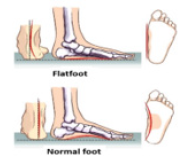

The flat foot is a common childhood condition which can cause pain and an altered gait. This pathology is determined by the fall of the plantar arch and the valgus pronation of the heel. It tends to lean towards the inside and the rest of the foot tends to point outwards causing the pathology (Figure 1&2) [5,6].

In the first phase of walking, up to 3 years, this condition is completely normal and is part of the physiological growth of the foot. After the age of 3, if the plantar arch isn’t correctly formed, an external action is required such as the use of an arch support. If this does not lead to an improvement of the plantar vault within 8-9 years, corrective surgery is recommended to be performed between 9 and 14 years. The flat foot determines an imbalance of the load at the level of the foot and an imbalance at the level of the posture, therefore can determine the occurrence of painful symptoms. Focusing on subjects of both sexes in infancy-adolescence age (8-16 years) suffering from congenital flat foot from tarsal synostosis, (Figure 3) shows the workflow of the traditional procedure. The main radiological procedure applied are: Radiology (RX) and Computed Tomography (CT). All radiological imaging techniques generally use X-ray beams to represent anatomical structures. The images generated by these methodologies are used to verify the presence of possible pathologies in the anatomical portion subjected to analysis. Of course, X-Ray exposition continues to represent a risk factor for the patient. X- rays produce ionizing radiation, a potentially harmful form of radiant energy. It must be emphasized that the risk of developing cancer following exposure to radiation it is generally contained and depends on at least two factors: